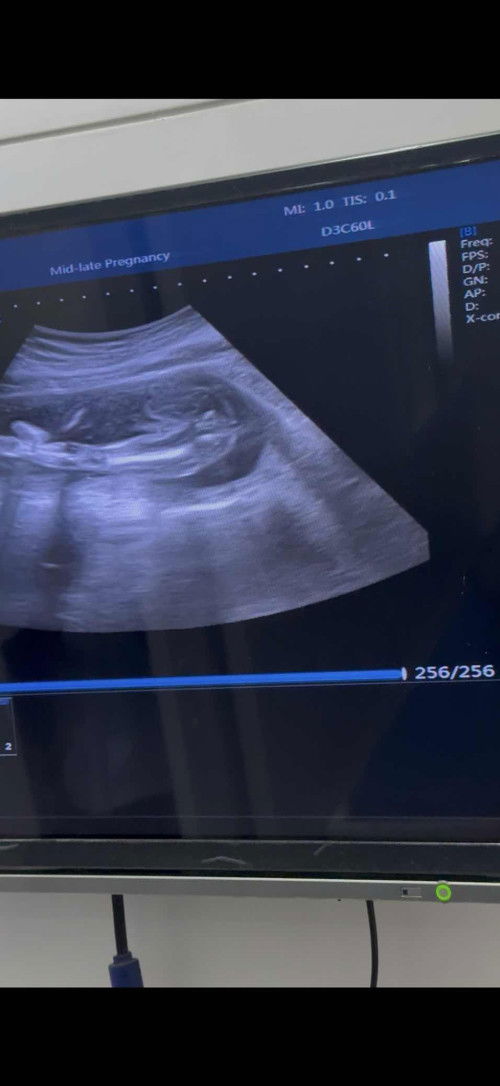

Birthclub: เมษายน 2026

6mo trước

• Chia sẻ

ควาทยาวของขา

น้องจะตัวเล็กมั้ยคะ 21W ค่ะ